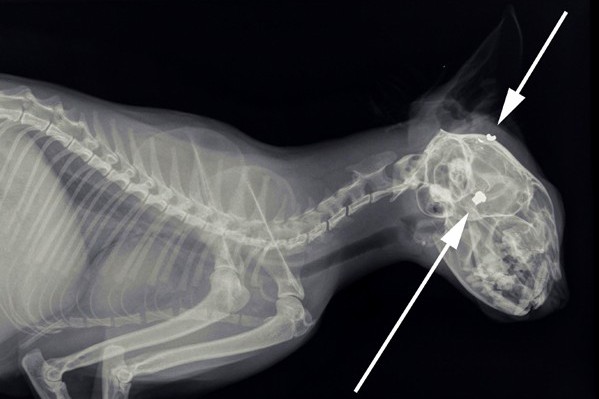

In de nacht van 14 op 15 november werd er bij de Dierenambulance een overleden kat aangeboden, die in een achtertuin in Maurik was gevonden. Het diertje, wat verder in zeer goede conditie leek te zijn, had een klein rond gaatje achter het rechter oor. De Dierenambulance bracht de kat bij onze dierenarts om een röntgenfoto te laten maken. Hiermee konden we vaststellen of het dier beschoten was. Een wondje zoals deze kat liet zien betekent namelijk niet automatisch een kogelgaatje. Zoals op de foto te zien is, is er dus inderdaad een kat beschoten in Maurik. In de schedel zijn één kogel en één kogelfragmentje aanwezig.